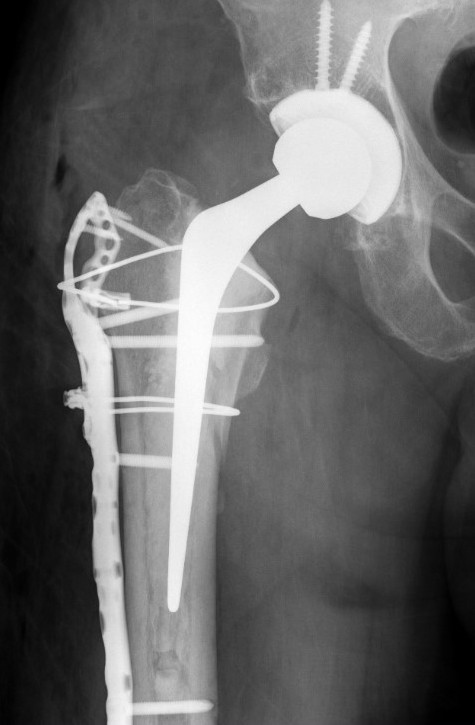

Revision uncemented arthroplasty with Zimmer cable plate

Long stem uncemented revision with cortical strut allograft

Long stem uncemented revision with plate + cortical struts